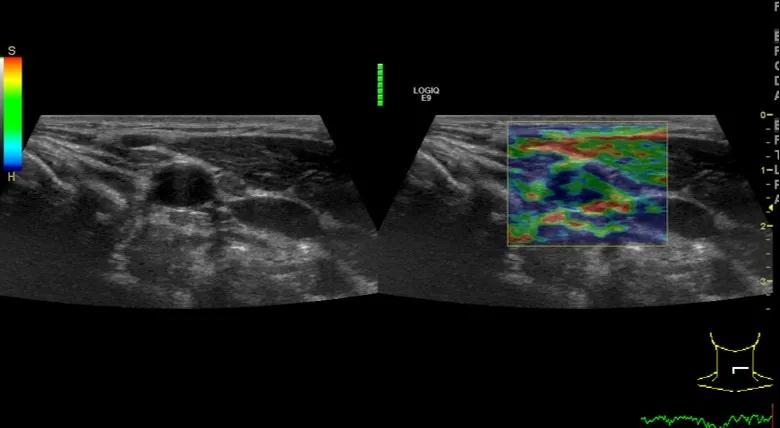

第三例是甲状腺癌患者,双侧甲状腺癌切除术后、碘治疗后一年余效果欠佳,超声显示左颈3区3枚低回声结节,穿刺示甲状腺乳头状癌转移。患者不愿意手术,希望采取局部治疗。对病灶进行液体隔离后采取热消融术,由于淋巴结较小,热消融一分钟左右完全灭活,术后增强影像显示没有脏器充填。

(病例3图例)